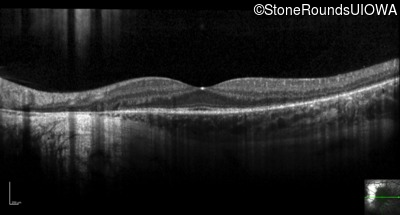

Optical Coherence Tomography - Right - 20/20 +1

Exemplar / OCT Stack

Optical Coherence Tomography - Left - 20/16 -2